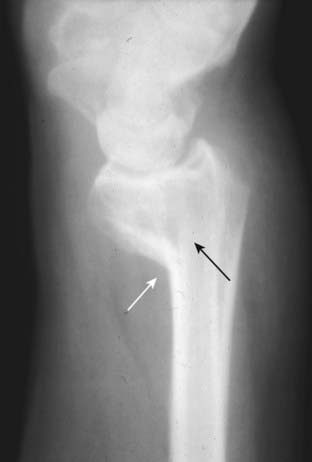

Figure 22-21 Colles’ fracture, frontal (A) and lateral (B) views.

Colles’ fractures are fractures of the distal radius (solid white arrows) with dorsal angulation of the distal radial fracture fragments (solid black arrow) caused by a fall on the outstretched hand (sometimes abbreviated as FOOSH). There is frequently an associated fracture of the ulnar styloid (dotted white arrow).

Figure 22-22 Smith’s fracture.

A Smith fracture is a fracture of the distal radius (solid white arrow) with palmar angulation of the distal radial fracture fragment (solid black arrow), the reverse of a Colles fracture. It is caused by a fall on the back of the flexed hand.